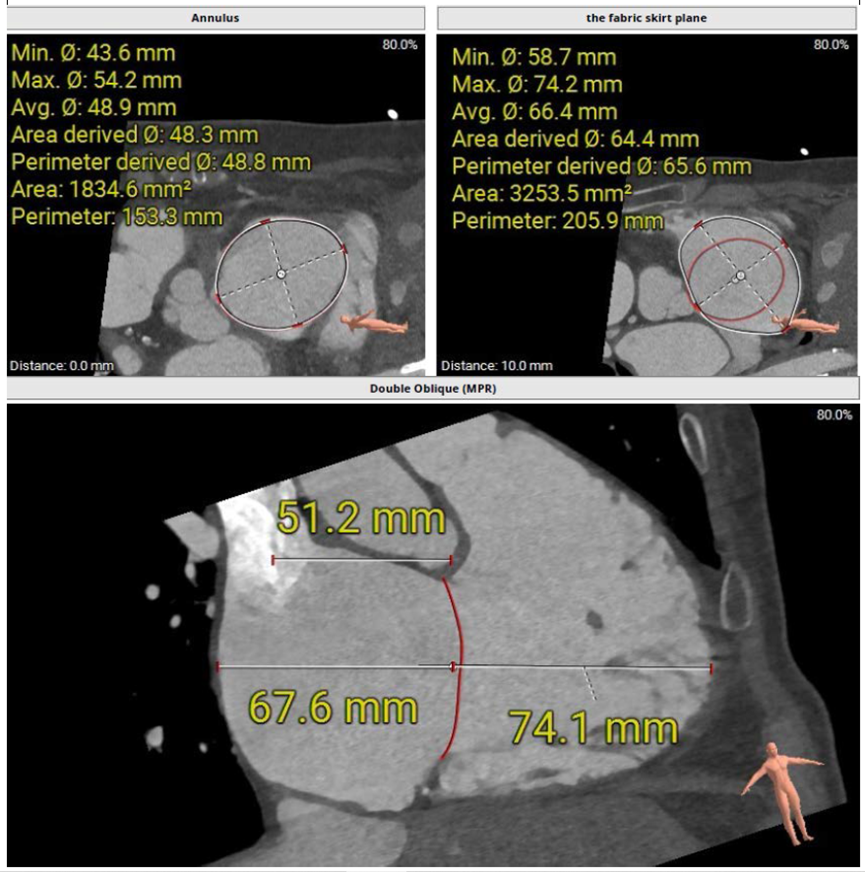

術(shù)前CT評(píng)估三尖瓣瓣環(huán)大小